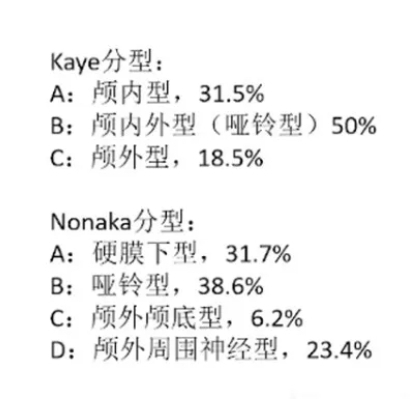

舌下神经鞘瘤分型